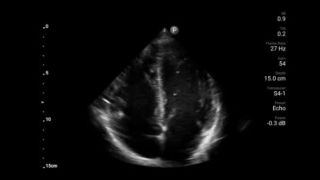

Transductor de disposición en fase de banda ancha Lumify S4-1

• Rango extendido de frecuencias de operación de 4 a 1 MHz • 2D, Doppler a color, Modalidad M, XRES avanzado e imágenes armónicas multivariables • Imagenología de alta resolución para aplicaciones abdominales y cardíacas: optimizaciones de preajustes de imágenes cardíacas, gineco-obstétricas, pulmonares, abdominales y FAST.

Ultrasonido cardíaco en el punto de atención prehospitalario: embolia pulmonar